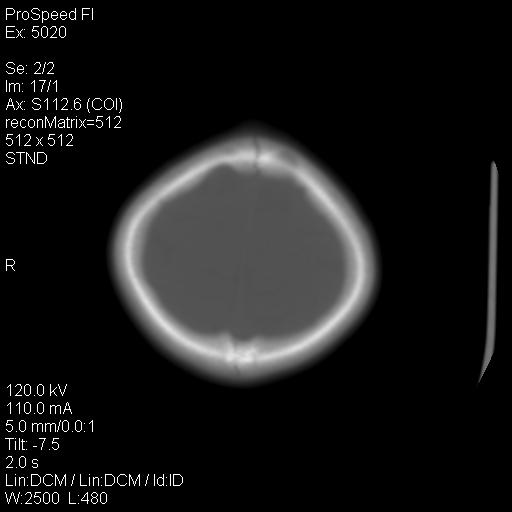

标题: PED1637:M 6Y 顶部无痛性包块两月。 [打印本页]

标题: PED1637:M 6Y 顶部无痛性包块两月。

2、颅骨局部缺失,边缘光滑、整齐

颅骨的病损表现为内外颅骨板层不规则的锋利的破坏,形成“斜边缘”,有一定的特点

颅骨为好发部位,生长缓慢,常位于顶骨、枕骨及颞骨,表现为颅骨缺损,呈圆形或椭圆形,边界清,无硬化